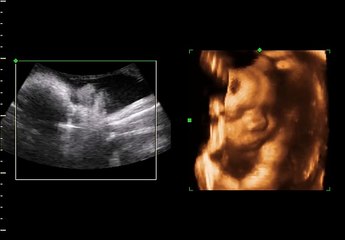

Is 3D4D Ultrasounds Safe During Pregnancy.

The only risk is that of the raised temperature. Its known scientific fact that the sound waves cause rise in temperature among the tissues they experience. This rise in temperature depends on the acoustic power and also the period of the scan.